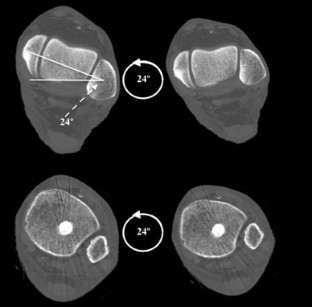

An intramedullary nail was placed in 14 skeletally mature legs. This included 8 patients with mid-shaft tibial fractures and 6 intact cadaveric legs. Each nail was a titanium cannulated tibial nail, size 10- or 11-mm. The nails were placed using a suprapatellar or transpatellar approach with an ideal starting point. All legs received post-nail insertion CT scans and fluoroscopy. The main outcome measure was the terminal location of the nail just proximal to the distal tibial physeal scar, as seen on axial CT and fluoroscopic views of the ankle (mortise and lateral). The end-point was measured as the (1) ratio of medial–lateral tibial width (ML ratio) and (2) ratio of anterior–posterior tibial width (AP ratio). Two-tailed Welch’s t tests were used to compare the actual, observed position of the nail to the hypothesized center–center position (H0 = ML and AP ratio of 0.5).

All enrolled patients (n = 8) and cadaveric legs were included (n = 6). On axial CT, the average distance from the medial tibial cortex to the nail center as a ratio of medial–lateral tibial width was 0.63, 95% CI 0.60–0.67, p < 0.001 (Patient = 0.60, 95% CI 0.55–0.64, p = 0.001) (Cadaver = 0.68, 95% CI 0.64–0.73, p < 0.001). On fluoroscopic mortise views, the distance from the medial cortex to the nail center as ratio of medial–lateral tibial width was 0.64, 95% CI 0.60–0.67, p < 0.001 (Patient = 0.61, 95% CI 0.56–0.65, p < 0.001) (Cadaver = 0.67, 95% CI 0.63–0.72, p < 0.001). The AP ratio was not significantly different from 0.5 on either axial CT or fluoroscopic mortise views (p > 0.05).